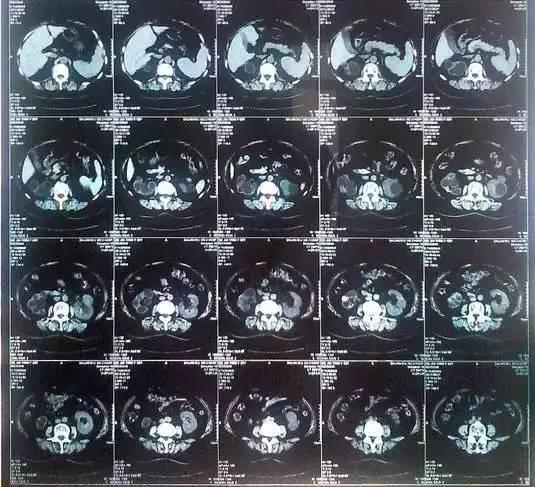

55歲的老何是金華東陽市橫店鎮(zhèn)人,一名普通工人。因為頻繁腰疼去醫(yī)院檢查,結果CT顯示,他的左腎里竟然密密麻麻布滿了石頭,幾乎把整個腎都塞滿了,手術從左腎取出了420顆結石!

醫(yī)生看了CT的結果顯示,非常嚴肅的告訴他,他的左腎已經(jīng)被結石占滿,必須馬上手術治療。這次手術讓主刀醫(yī)生觸目驚心,他們居然從老何的左腎取出了420顆結石。這是他們手術生涯上從來沒有遇到過的病例。